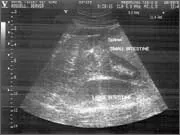

Thoracic and abdominal ultrasonography

This is a key diagnostic technique in the hospital and the technology has advanced to such a degree that we are able to image blood flowing within the heart and collagen fibre misalignment in tendons.